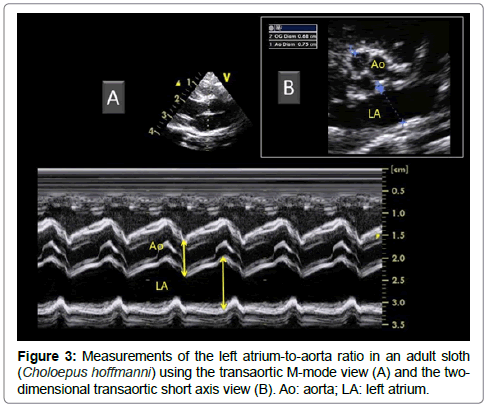

Once the appropriate position was found, the variability study was undertaken. A mean of 3 measurements was obtained for each M-mode ventricular parameter on 3 consecutive cardiac cycles on the same frame. Ventricular measurements (i.e., left ventricular (LV) end-diastolic and end-systolic diameters, LV free wall and interventricular septal thicknesses at end-diastole and end-systole) were taken from the right parasternal location using the 2D-guided M-mode (Figure 2), and the LV shortening fraction was then calculated [13-19]. Heart rate was also calculated from this M-mode view. The E point-to-septal separation was also measured using the 2D guided M-mode at the level of the mitral valve. Measurements of the aorta (Ao) and left atrium (LA) were made by two different methods (Figure 3), and the corresponding LA:Ao ratios were then calculated. One method consisted in measuring LA and Ao diameters at end-diastole, using the 2D short-axis right-sided parasternal view obtained at the level of the aortic valve where the commissures of the cusps could be visualized. The internal short-axis Ao diameter was measured along the commissure between the non-coronary and left coronary aortic valve cusps. The LA diameter was measured using the same frame, in a line extending from and parallel to the commissure between the non-coronary and left coronary aortic valve cusps. The second method consisted in using the 2D-guided M-mode from the 5-chamber long-axis view from the right parasternal location. The internal Ao diameter was measured from the corresponding M-mode view at end-diastole, and the internal LA diameter was measured at end-systole.